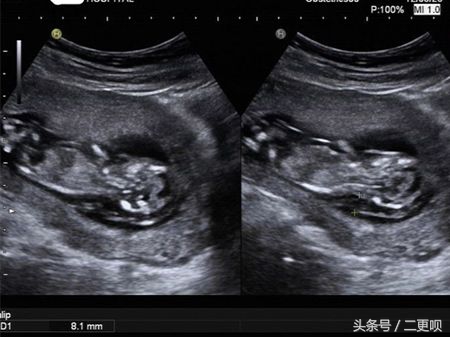

还好一切都正常 漫长的孕程我走了三分之一拉。附上NT B超图

NT是(nuchal translucecy, NT),是胎儿颈部半透明膜的缩写,是胎儿的第一次畸形排查。它的厚度与胎儿DS缺陷正相关,并可以通过超声成像测量。用于评估胎儿是否会患唐氏婴儿的一种。所以还在问到底要不要去做NT的准妈妈,不要再犹豫拉。为了宝宝健康!

准妈妈最好在孕11-14周内做NT最好,因为11周前由于胎儿太小,无法视察颈后透明带,而14周的过后胎儿会逐渐发育,可能会将颈项透明层出多余的体液吸收,影响检测结果。所以建议准妈妈在11-14周内去做NT。